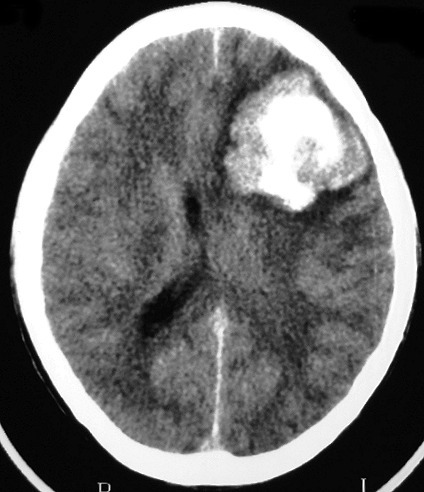

Qual a densidade do sangue fresco na TC?

hiperdenso

(imagem = TC de área hiperdensa com efeito de massa - hematoma frontal e recente)

Quais as indicações de TC?

É mais sensível em casos agudos, como TCE agudo, AVC agudo, cefaléia aguda grave, coma agudo.